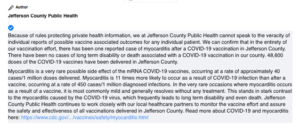

The CDC—which, like Berry, has swept this kind of devastating heart damage under the rug—has not investigated his death.

Berry and her fellow vaccine damage deniers would have you believe that most injuries and deaths following injection are coincidences. In one of her most incredible disinformation statements yet, she told us that since the rollout began a year ago there have been only ELEVEN deaths from all Covid shots across the U.S.: “I believe it’s 11 nationwide.” (“TOP TEN 2021 Spin Doctor Disinformation Statements”)

While the mainstream media works overtime to find and hype a single death from the Omicron virus, the millions of injuries and possibly hundreds of thousands of deaths from the experimental injections don’t make the news. Now and then a story that can’t be ignored—like the shots causing myocarditis in young people—is permitted in order to broadcast pharma’s spin assuring the public that it is “rare” and “mild”, two of Berry’s favorite terms to dismiss tragic outcomes.